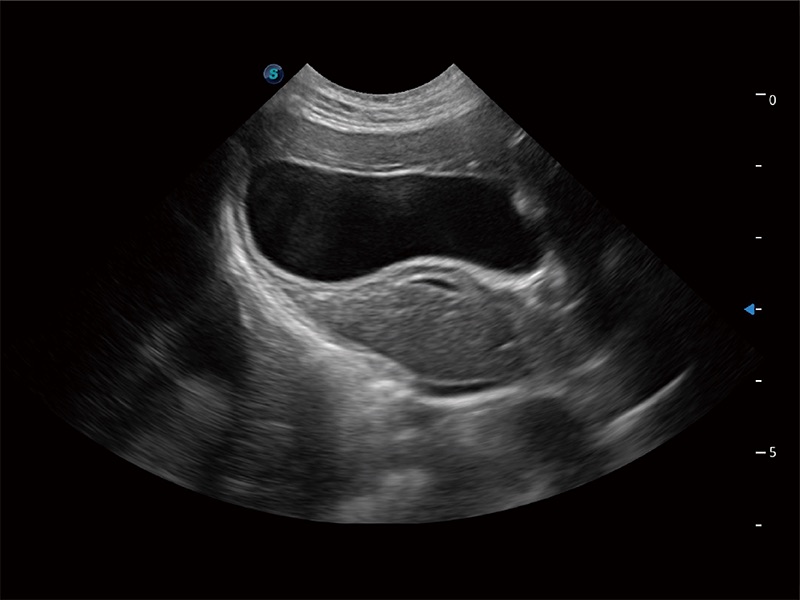

动物是人类最亲密的朋友和最值得信赖的伙伴。新葡的京集团8814检测站也一直致力于探索动物专用的超声影像解决方案。全新推出的ProPet系列,是新葡的京集团8814检测站在动物超声影像智能化、专业化、精准化的一次跨越式革新。动物不能用言语来表述自己的不适,通过超声影像,ProPet系列搭建了动物医生与不同物种沟通的“桥梁”,为动物医生注入了“治愈之力”。 ProPet 80 是新葡的京集团8814检测站匠心打造的一款高端动物专用彩超,采用性能卓越的全新硬件架构,极大提升超声系统的运行效率和数据处理能力,帮助动物医生从容应对日益增多的挑战性病例和日益多样化的临床需求。

高性能和先进的临床应用工具可以为动物医生提供临床信心。ProPet 80 搭载了先进的腹部和浅表应用工具,帮助医生在日常临床实践中发挥前所未有的作用。

ProPet 80 全新的动物超声智能软件和丰富的探头群,为动物医生提供了高清晰度和精细分辨率的图像,无论在宠物、马科、畜牧还是实验室动物等应用中都可以轻松应对,为您的日常工作带来满意的体验。